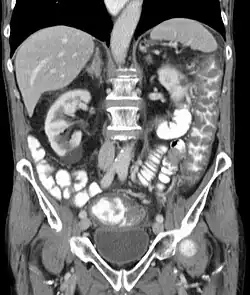

| Complications | Pseudomembranous colitis, toxic megacolon, perforation of the colon, sepsis[1] |

Clostridioides difficile infection[5] (CDI or C-diff), also known as Clostridium difficile infection, is a symptomatic infection due to the spore-forming bacterium Clostridioides difficile.[6] Symptoms include watery diarrhea, fever, nausea, and abdominal pain.[1] It makes up about 20% of cases of antibiotic-associated diarrhea.[1] Antibiotics can contribute to detrimental changes in gut microbiota; specifically, they decrease short-chain fatty acid absorption, which results in osmotic, or watery, diarrhea.[7] Complications may include pseudomembranous colitis, toxic megacolon, perforation of the colon, and sepsis.[1]

In those with severe C. difficile colitis, colectomy may improve the outcomes.[97] Specific criteria may be used to determine who will benefit most from surgery.[98]